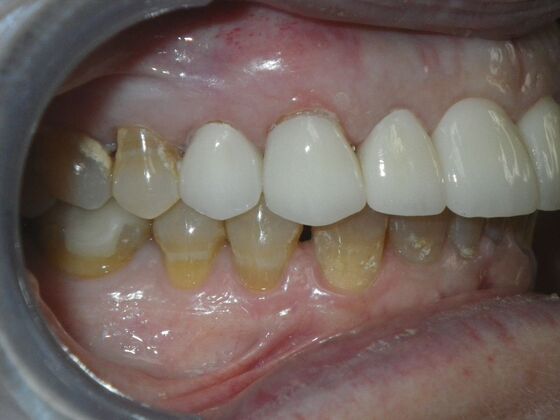

Cosmetic Changes with Veneers and Crown and Bridge: Case 1

Patient presented with spacing between upper central incisors and dark tetracycline stains that she wanted corrected